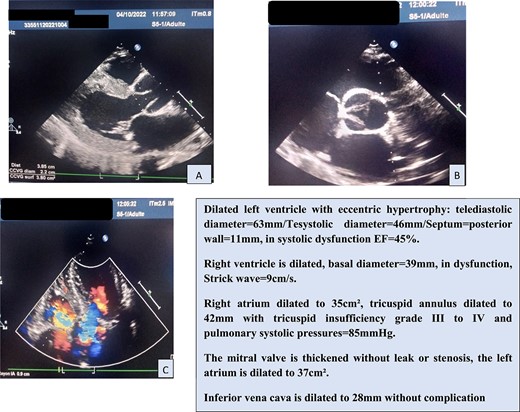

In view of this clinical picture, transthoracic echocardiography (TTE) was performed, which confirmed the significant AI and ascending aorta dilatation (Fig. 1).

The aneurysmal dilatation is only on the supratubal aorta, preserving the aortic annulus and the sinus of valsalva. This is a type 1 IA that causes traction on the cusps at the level of the STJ, resulting in central diastasis and aortic leakage.